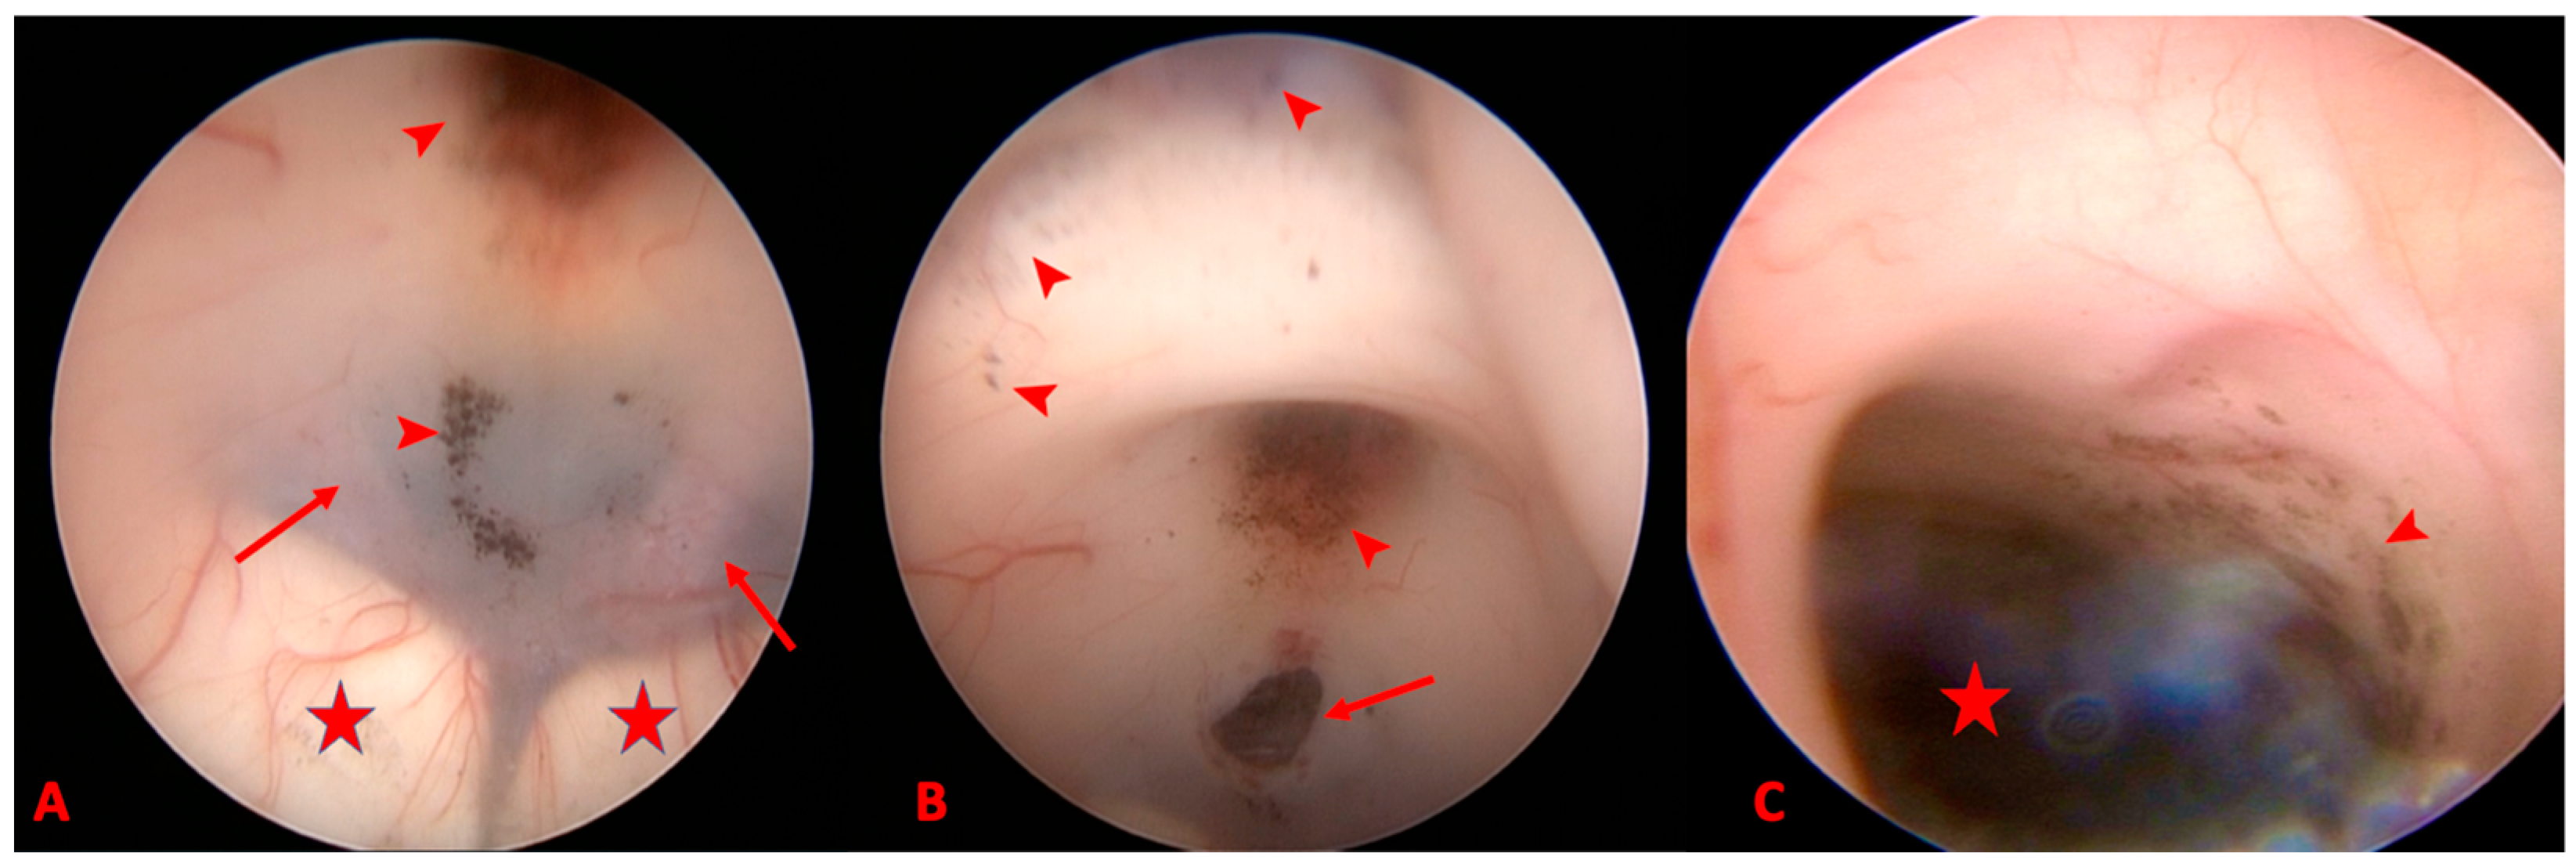

2. Detailed Case Description

3.2.2. MRI